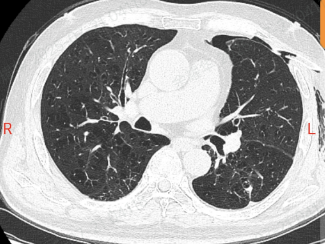

他这肺就像个漏气的气球,气胸反反复复,隔几周就得住院抽气、插管子,CT 片上的肺大疱密密麻麻,医生说这是难治性气胸,传统手术风险不小。

手术前,团队用 3D 成像把病灶看得清清楚楚。

进了手术室,高清胸腔镜像 “放大镜” 一样找到漏口,医生精准修补后,又用上可吸收的生物材料 “补丁”,最后注入自体血促进恢复。

术后第三天,老李就能带着引流瓶在走廊慢慢走了;第七天复查,肺终于好好张开了,那根带了一年的引流管终于拔掉了。